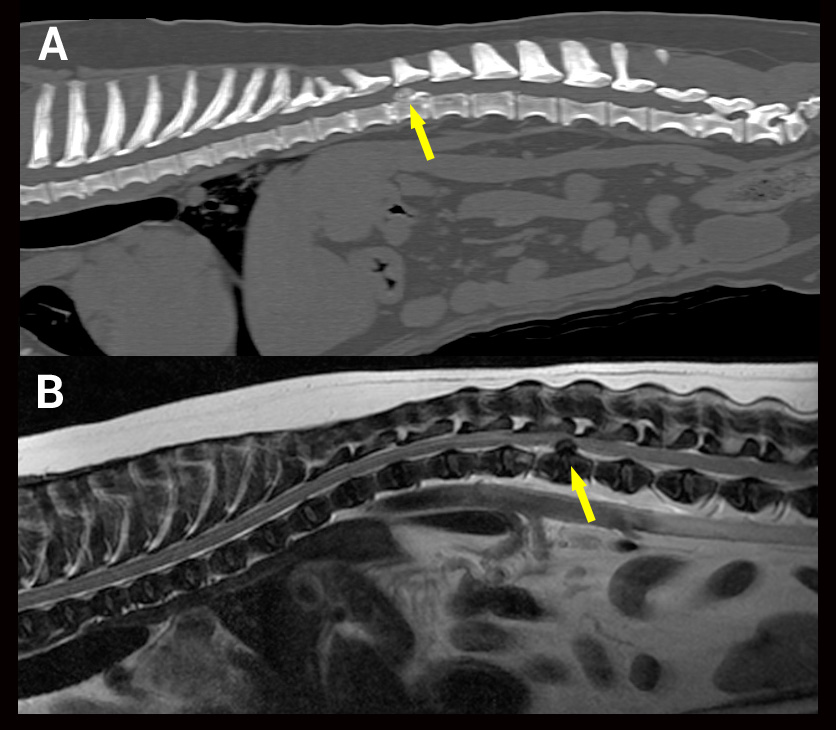

Comparaison CT-MR hernie type I